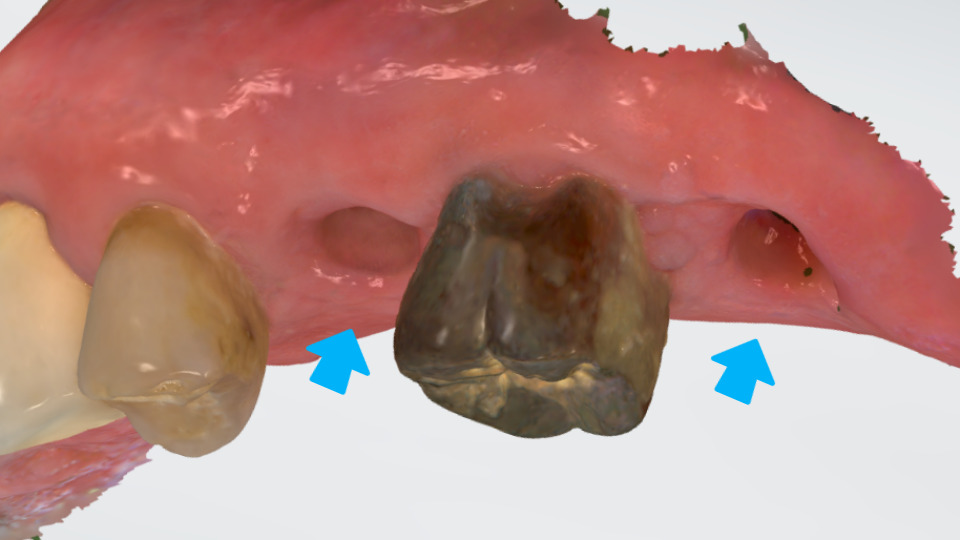

또 한가지 신경 쓴 부분은

바로 씹을 때 강한 힘이

필요한 어금니라는

것인데요.

서울바르치과는 사진과 같이

자연스러운 치아색으로

예쁜 모양을 가지면서,

쉽게 깨지지 않는

단단한 치과 재료인

지르코니아(Zirconia)를

사용해 크라운 제작을

의뢰했습니다.

씹는 면의 섬세한

주름까지 정교한 구현이

가능하여 최근 사랑받는

치과 신소재랍니다.^^